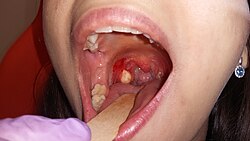

Als lokales Verfahren, auch Kryochirurgie bezeichnet, kommen Gefriertechniken mit sehr niedrigen Temperaturen zum Einsatz, um eine Zerstörung krankhaft veränderter Gewebe zu erreichen. Man unterscheidet geschlossene Verfahren, bei denen eine Kältesonde von außen mit dem Gewebe in Kontakt gebracht wird, von offenen Verfahrensweisen, bei denen Kühlmittel direkt ins Gewebe eingebracht werden (häufig Flüssigstickstoff bei −196 °C). Der Arbeitsbereich liegt bei −70 °C bis −200 °C. Derartige Verfahren werden in der Dermatologie angewandt, um Tumoren, Warzen (Viruspapillome), überschießendes Narbengewebe (Keloid) und verschiedene andere Gewebserkrankungen zu entfernen.[11][12] Darüber hinaus findet die Kryochirurgie auch bei interventionellen Therapieverfahren von anderen Tumoren Anwendung, wie etwa zur Therapie von Lebermetastasen[13] sowie eventuell bei Lungen- oder Prostatatumoren.[14] Metastasen und Tumore sollten für den Einsatz der Kryotherapie nicht größer als fünf Zentimeter und lokal begrenzt sein, da diese Behandlung besonders bei kleinen Tumoren effektiv ist; außerdem spielt die Lage eine wesentliche Rolle. Als Nebenwirkungen können Schmerzen oder Nebenwirkungen an der Einstichstelle, in seltenen Fällen auch Komplikationen wie Schädigungen am Gewebe und den Nerven rund um die vereiste Stelle auftreten.[15]

Used nitrospray on both tonsils (-196C) | Eigenes Werk | Cryosurgery | Datei:Cryosurgery.jpg | |